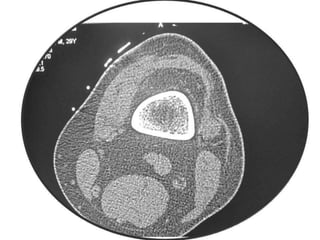

Osteoid Osteoma - CT

• CT is more accurate than MRI.

• CT helped in confirming the diagnosis of

osteoid osteoma in 74% of cases.

• Szendroi et al reported accuracies of about

66% in the diagnosis of intra-articular lesions

and 90% in extra-articular lesions.

• To date, CT scanning is the primary

investigational tool for the definitive diagnosis

of osteoid osteoma.